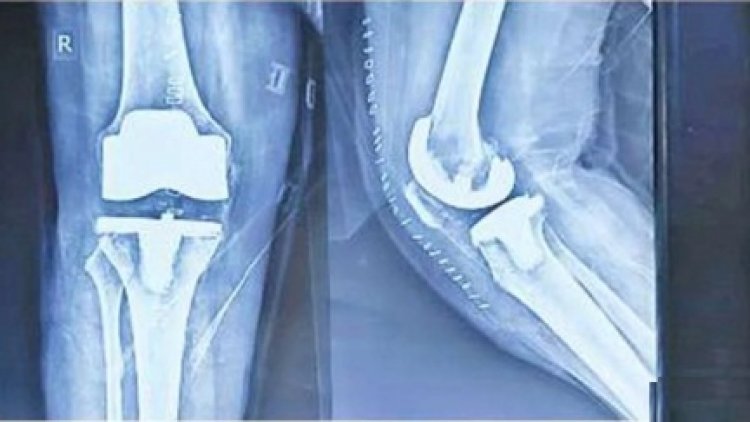

बिलासपुर: सिम्स अस्पताल के अस्थी रोग विभाग में लगातार घुटना और कूल्हे के जोड़ों का प्रत्यारोपण किया जा रहा है, जो आर्थिक रूप से कमजोर मरीज़ों के लिए वरदान साबित हो रहा है। इसी कड़ी में एक 65 वर्षीय महिला का भी सफलता पूर्वक ऑपरेशन किया गया है। बुजुर्ग महिला का दायां घुटना पूरी तरह से खराब हो चुका था और चलना-फिरना बंद हो चुका था। सर्जरी कर उसकी समस्या को दूर करते हुए चलने लायक बनाने का काम सिम्स के चिकित्सकों ने किया है। जिसके बाद महिला के लिए जीवन एक बार फिर आसान हो गया है।